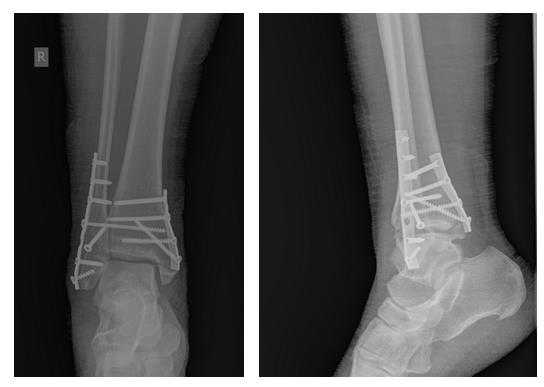

Рис. 10. На рентгенограмме левой стопы в прямой и боковой проекциях определяется удовлетворительное стояние костных фрагментов на фоне металлофиксатора

На контрольных рентгенограммах после операции положение отломков, металлофиксаторов правильное, подвывих таранной кости устранён.